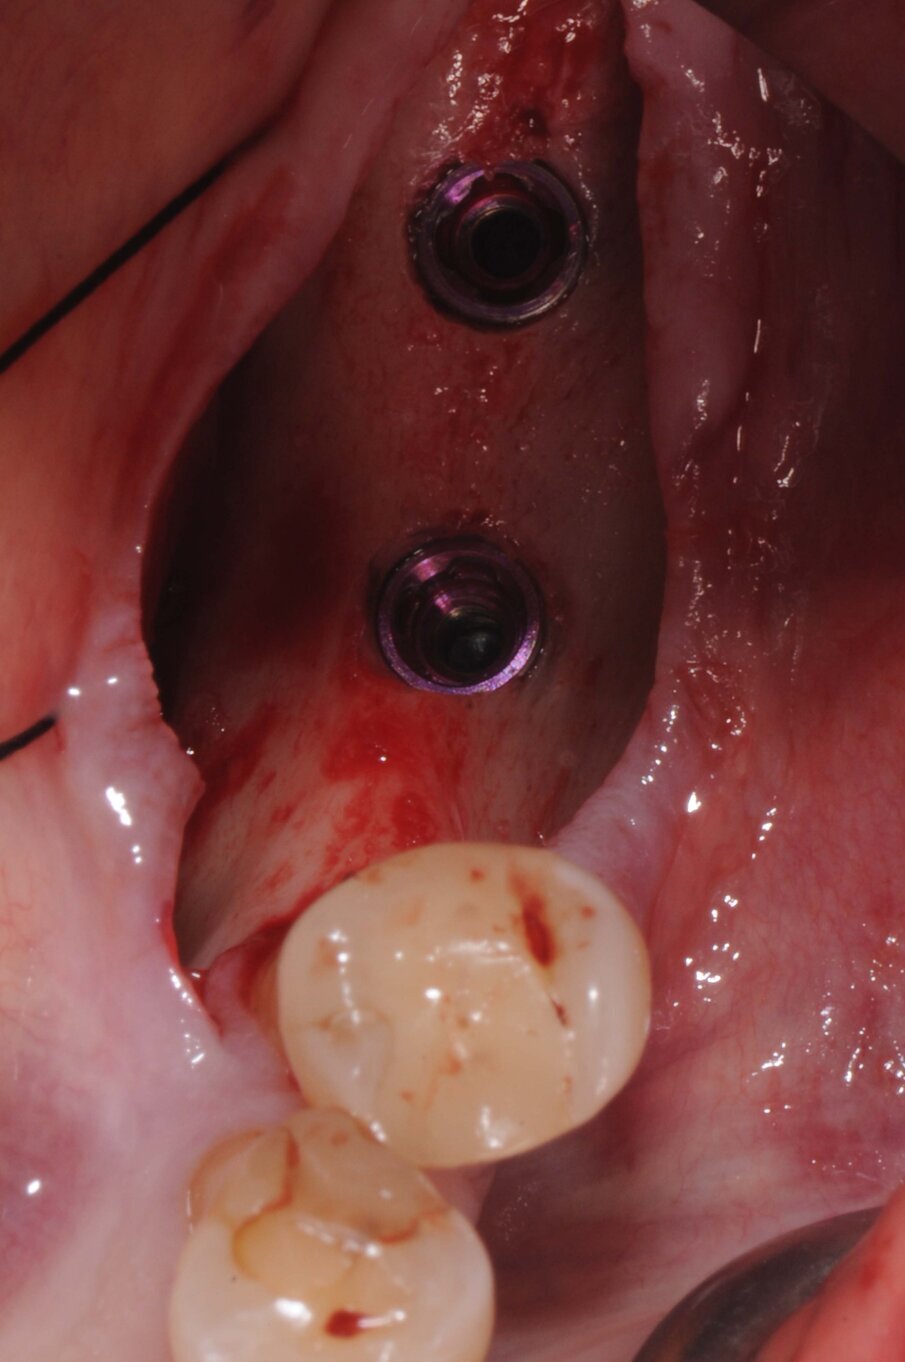

Scopertura impianti

Dopo due mesi senza complicazioni fu eseguita un’incisione crestale e i due impianti furono scoperti. Si notò una ricrescita di osso al di sopra degli impianti che fu rimossa con una fresa a palla diamantata. Furono avvitati due pilastri Multi-Im sugli impianti e fu eseguita una sutura per accollare i lembi (Figg. 8, 9).